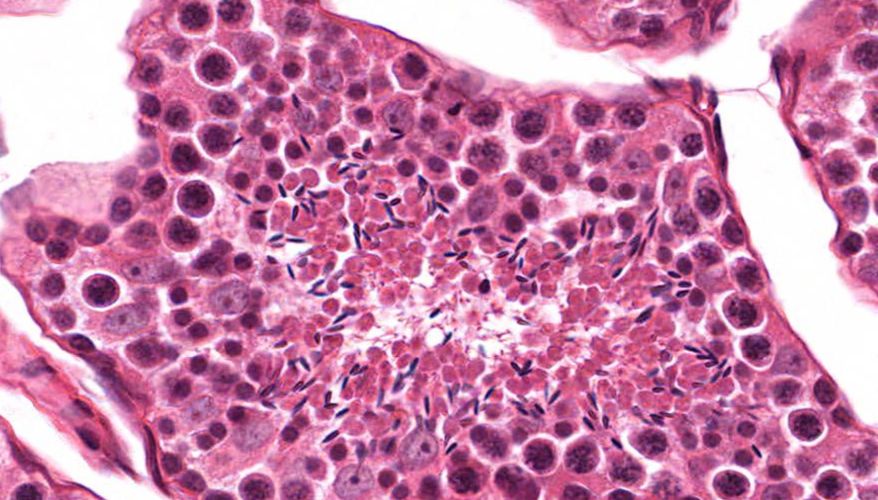

低倍镜:睾丸表面为鞘膜覆盖,其上皮为单层扁平上皮,鞘膜下是一层较厚的致密结缔组织,叫做白膜。白膜在睾丸后缘增厚,形成睾丸纵隔,其内可见不规则的腔隙,即睾丸网。睾丸内可见很多上皮性管道的切面,即生精小管的切面,呈圆形或椭圆形,管壁较厚,由生精上皮及其明显的基膜等组成。高倍镜:着重观察生精小管和其之间的睾丸间质。生精小管主要由生精上皮构成。生精上皮由生精细胞和支持细胞组成。生精细胞是一组细胞,依次自基膜向管腔面排列。

6.生精上皮

7.支持细胞

8.精原细胞

9.初级精母细胞

10.精子细胞

11.精子

15.精子发生